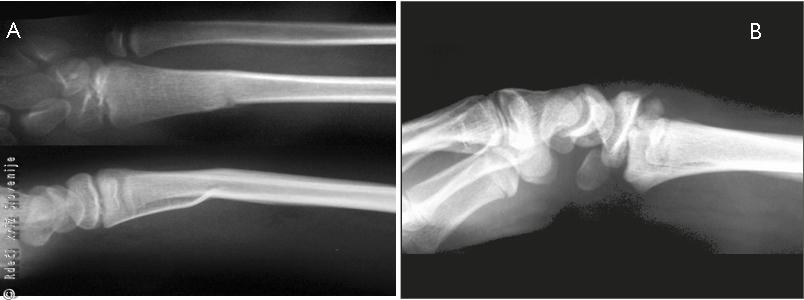

Slika 7

Najpogostejši poškodbi skeleta pri otrocih sta subperiostalni zlom in epifizioliza.

A – Subperiostalni zlom podlahti.

B – Epifizioliza spodnjega dela koželjnice.

Primer 1

12-letna deklica se je na prigovarjanje vrstnikov s kotalkami spustila vzvratno po cesti navzdol. Ob tem je zgubila ravnotežje, padla in se ujela na iztegnjeno dlan. Zaščitne opreme ni imela. Roka jo je pričela zelo boleti in pojavila se je naraščajoča oteklina. Gibaje v zapestju je bilo zaradi bolečine povsem zavrto. Deklica si je roko vseskozi podpirala z nepoškodovano roko. Vrstniki so jo pospremili domov, kjer ji je mama namestila ruto in oteklo mesto hladila z brisačo namočeno v hladno vodo. Ker se je bolečina stopnjevala jo je odpeljala v urgentno službo bližnje bolnišnice. Po pregledu in rentgenskem slikanju so ugotovili, da ima zlom koželjnice na značilnem mestu. Napravili so uravnavo zloma v splošni anesteziji. Deklica je dobila doramenski mavec. Nato so oskrbeli še rane na obeh kolenih.

Slika 8

A – Nepravilna oblika zapestja.

B – RTG znaki zloma koželjnice na značilnem mestu.